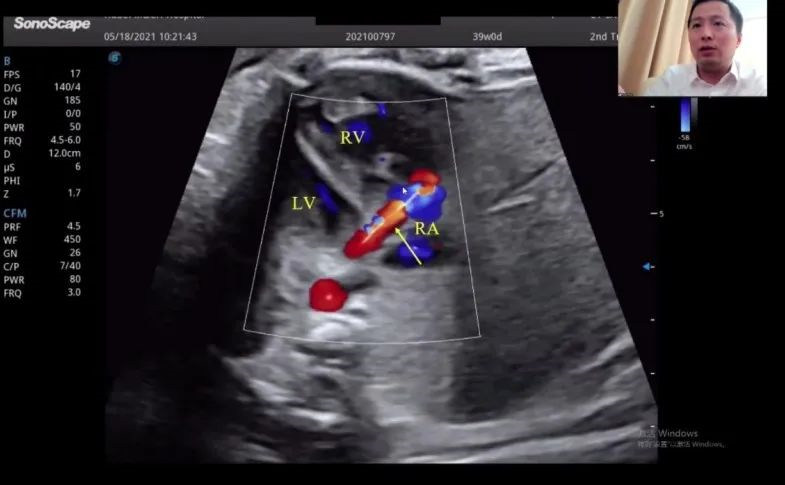

湖北省婦幼保健院的趙勝教授在會(huì)上帶來(lái)了胎兒冠狀動(dòng)脈瘺超聲診斷研究的分享。趙教授表示,冠狀動(dòng)脈瘺在妊娠晚期可通過(guò)超聲檢查顯示出來(lái),經(jīng)線(xiàn)圈栓塞或冠狀動(dòng)脈瘺術(shù)后,進(jìn)一步的臨床過(guò)程通常較為順利。